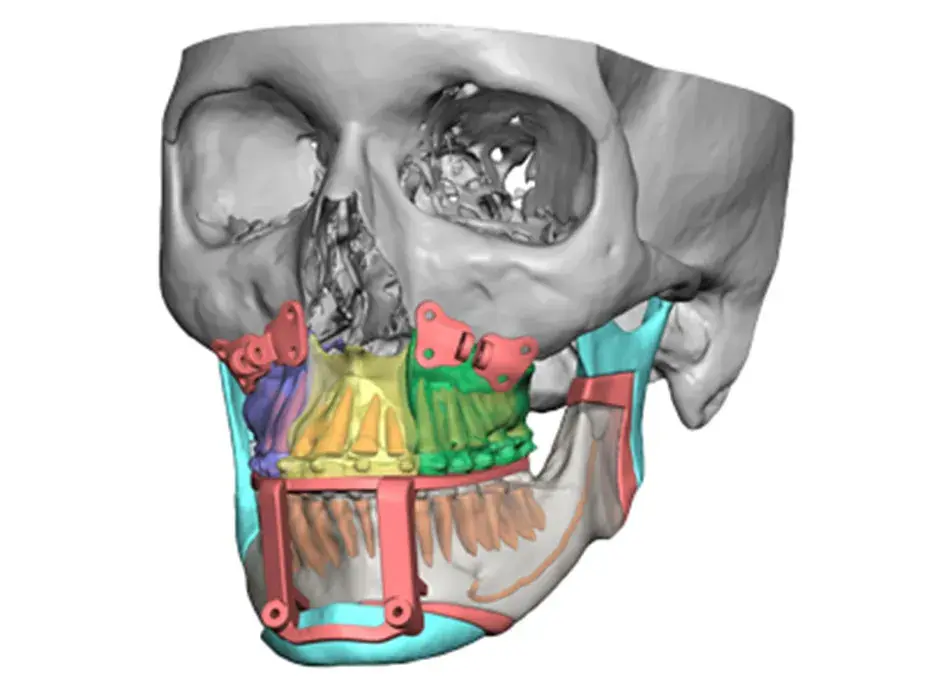

3D Systems' VSP® surgical planning solutions for craniomaxillofacial (CMF) applications received FDA clearance as a service-based approach to personalized surgery over 10 years ago.

3D Systems and Stryker Corporation have partnered to provide surgeons with best-in-class products and services for craniomaxillofacial surgeries. As a leader in personalized healthcare solutions, 3D Systems has planned and delivered devices for more than 140,000 patient-specific cases. The Stryker Craniomaxillofacial business specializes in providing patient-specific options and innovative solutions that help drive efficiencies in surgical suites. The combination of Stryker’s specialized team and advanced implants with 3D Systems' cutting-edge 3D printing technologies and expert consulting services positions both companies to provide a superior level of service to healthcare professionals who use these revolutionary solutions.